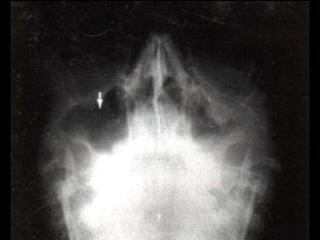

Lesiones Craneales

XXX

Hematoma

subgaleal

Fractura craneal y

hemorragia subdural

Fractura

Hemorragia Subaracnoidea

Fractura craneal